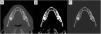

Materials and methods

We analysed 20 patients who underwent multidetector computed tomography to evaluate mandibular bone and tooth positioning. Image analysis included automatic segmentation of the mandible, obtainment of sections perpendicular to the dental arch, and structural analysis of the trabecular bone in each section. We calculated the ratio between the volume of bone and the total volume of the section, the thickness, the trabecular number, and the mean attenuation in Hounsfield units. We analysed the differences among different tooth types (incisors, canines, premolars, and molars) and between present and absent teeth.